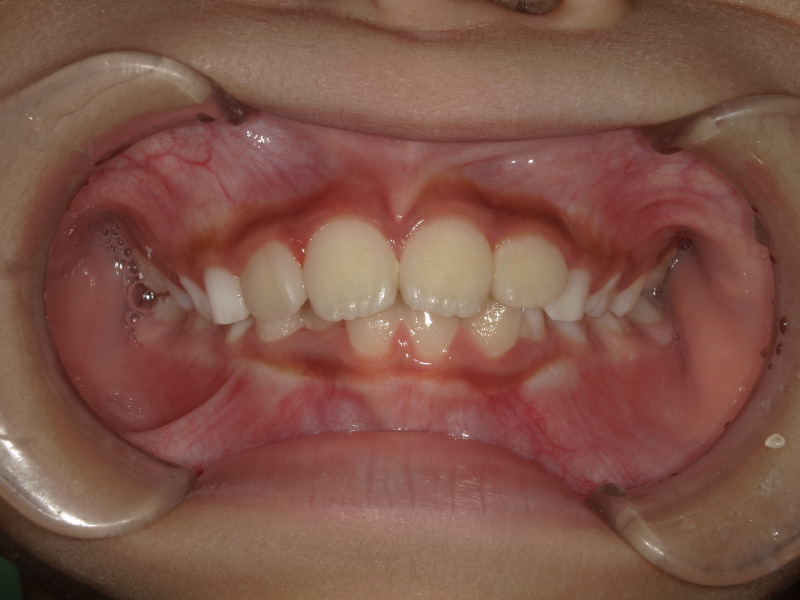

治療開始時

最初の検査時に撮影した写真です。

お母さんが気にされていた前歯が大きいという点ですが、歯が大きく見えるのは噛み合わせの状態や、顎の骨の成長が足りていないケースも考えられます。

下の歯が隠れており、前歯の存在が大きく感じます。

下の歯並びは2番目の歯が後ろから生えてきており、スペースが足りないようでした。